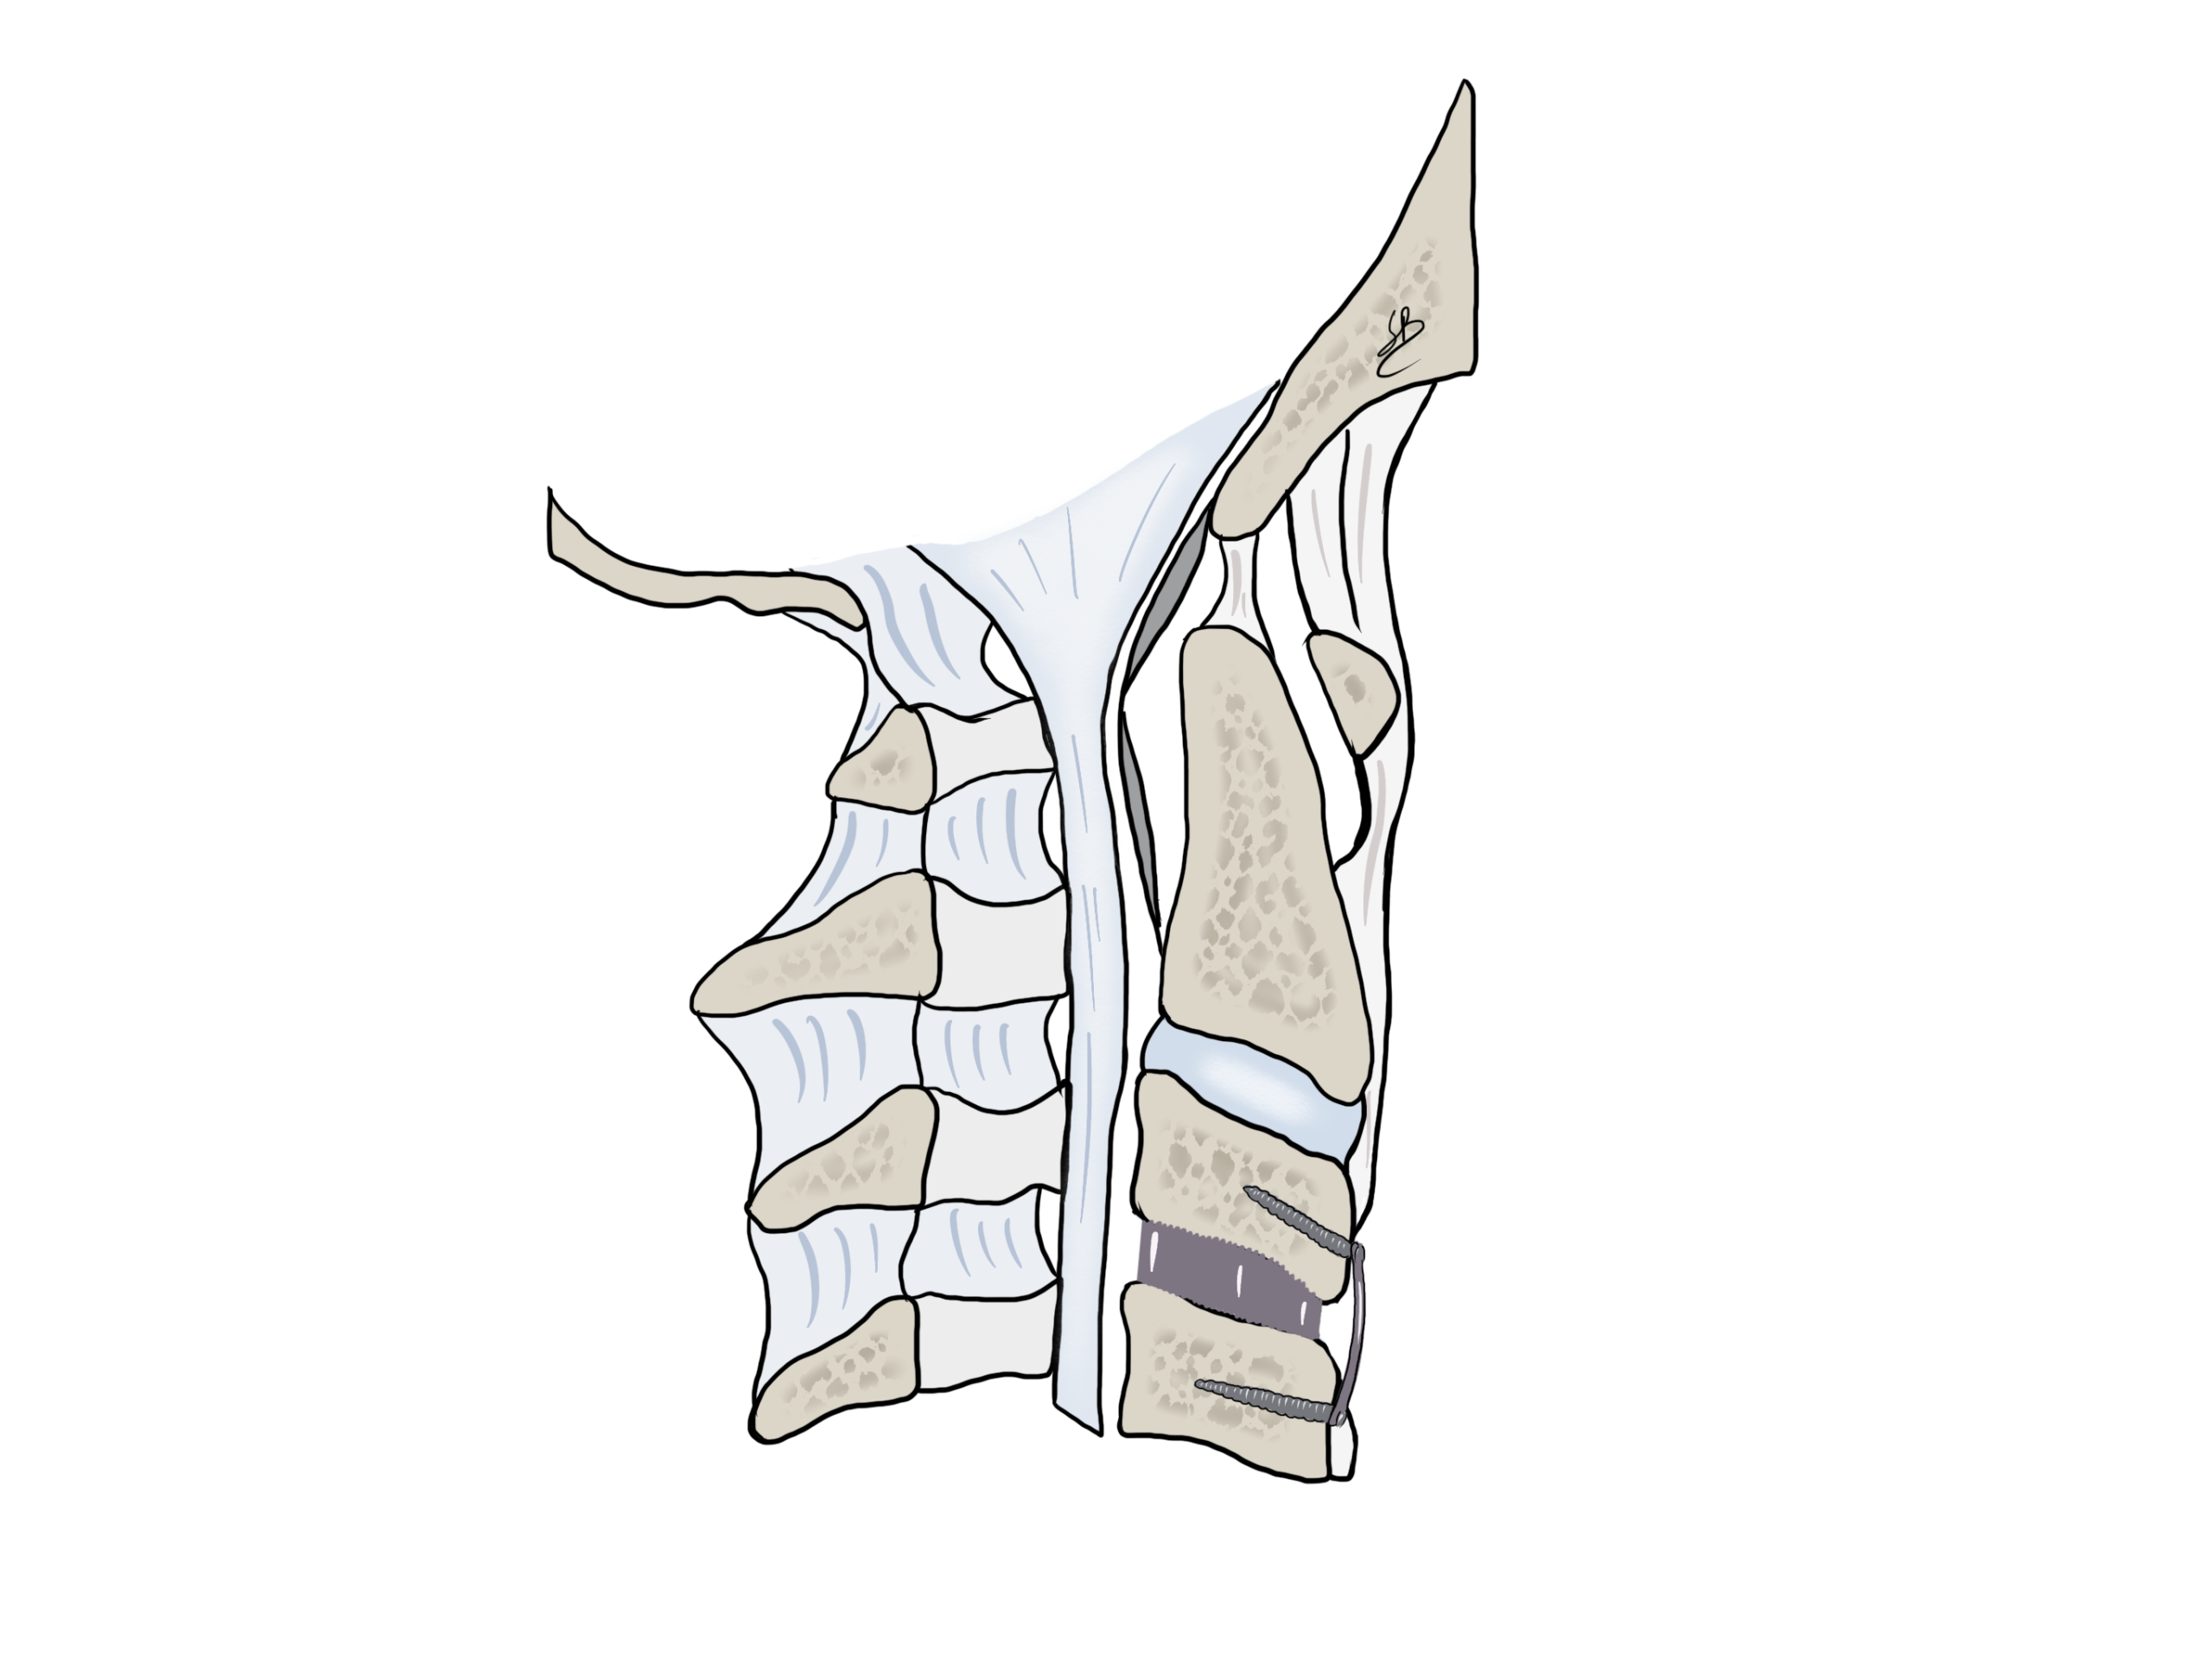

Se i metodi conservativi non portano alcun beneficio, l’intervento chirurgico diventa indicato. Si tratta di una decompressione del nervo asportando l’ernia discale per via anteriore. Il disco malato è rimosso e rimpiazzato da una gabbietta di titanio. L’intervento dura 1 ora circa sotto anestesia totale. Il Dr Robert e la Dr.ssa Bonasia fanno questo tipo di intervento in maniera mininvasiva e microscopica per limitare al massimo l’apertura cutanea (2 cm circa) ed il traumatismo muscolare para-vertebrale. Presentano un’esperienza di più di 200 casi operati con questa tecnica.

Approccio cervicale anteriore per discectomia ACDF

Dopo il trattamento chirurgico di ernia discale cervicale, il paziente segue un ciclo di fisioterapia per rilassare la muscolatura para-vertebrale e riprende progressivamente le sue abitudini quotidiane in 1 mese circa. Proponiamo dei controlli ambulatori per un periodo di 1 anno dopo questo tipo di intervento.